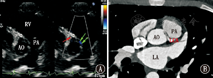

11例病例中超声心动图确诊10例,漏诊1例。超声诊断为左冠状动脉起源于右冠状窦并壁内走行4例(图1),右冠状动脉起源于左冠状窦6例(壁内走行2例,大动脉间走行4例)(图2)。超声心动图可清晰显示病变冠状动脉是否壁内走行等情况。1例合并完全性肺静脉异位引流者超声心动图检查未发现冠状动脉起源异常。

注:AO:主动脉;PA:肺动脉;RV:右心室;LCA:左冠状动脉;A:超声心动图大动脉短轴切面,可见左冠状动脉自右冠窦发出,沿主动脉壁内走行(双箭头所示),右冠状动脉开口位置正常(单箭头所示);B:左冠状动脉起源于右冠状窦心脏CT所见 AO:aorta;PA:pulmonary artery;RV:right ventricle;LCA:left coronary artery;A:transthoracic echocardiography shows the normal origin of the right coronary artery (single arrow) and anomalous left coronary artery running intramural within the anterior aortic wall (double arrows);B:multislice computed tomography image shows anomalous origin of the left coronary artery from the right sinus

11例病例行心脏多层螺旋CT检查,5例为左冠状动脉起源于右冠状窦(图1);6例为右冠状动脉起源于左冠状窦。